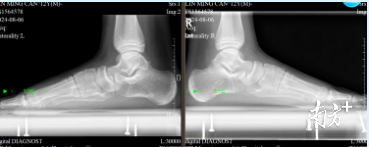

▲患者术前X片。

“经过检查,这个小朋友的双足内侧足弓塌陷严重,舟骨结节突出,负重位后足已经有些外翻畸形了。”肖进说,“这是很典型的儿童柔软性平足症,也是我们常说的扁平足畸形。而这个小朋友由于以前拖的时间有点长,没有在早期接受治疗,导致现在症状已经有些严重了。”